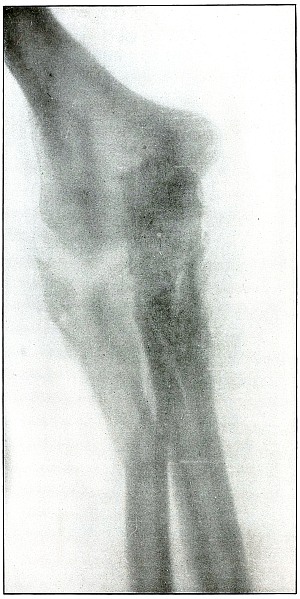

Plate 19.

[Pg 49]

Rifle—Plate 19.

UPPER EXTREMITY.

Gunshot Fracture of the Elbow,

without Injury to the Great Vessels and Nerves.

This is a plate made of the same subject shown in plate 18, when convalescence was several weeks

farther advanced, as is indicated by the removal of fragments and

extensive callus formation.

Both radiographs were made after the apprehension of systemic

infection had passed; the second plate after an additional number of

fragments had been removed.

[Pg 50]